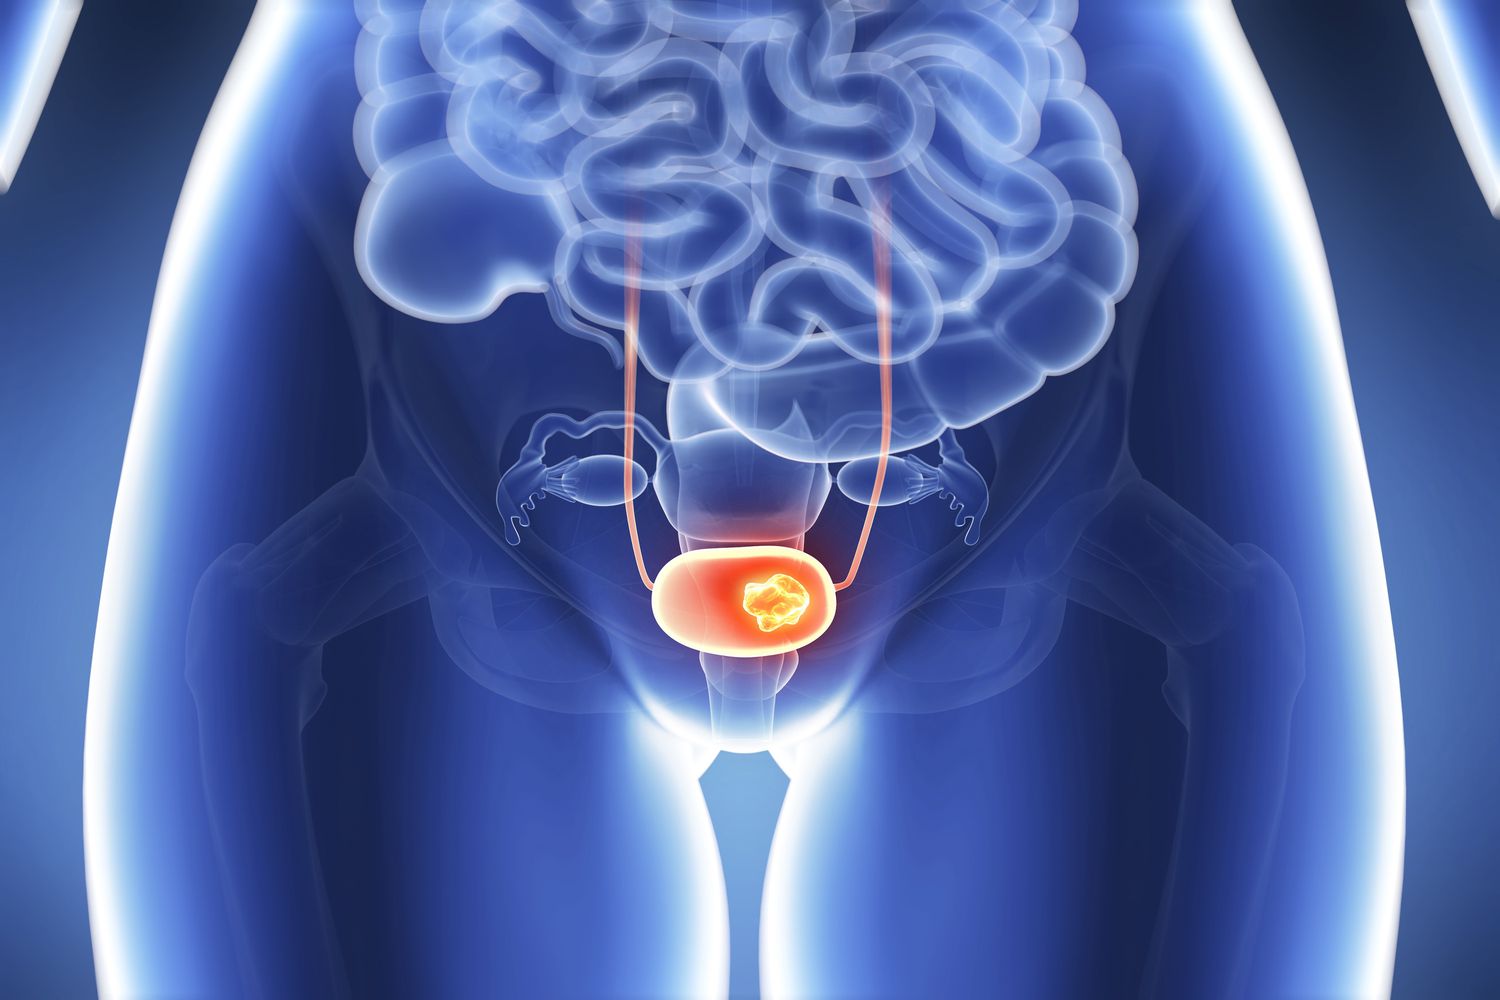

Kadınlarda Mesane Kanseri

Kadınlarda mesane kanseri, idrar torbasında başlayan bir kanser türüdür. Bu hastalık, kadınlarda genellikle daha nadir görülmekle birlikte, özellikle ileri yaşlarda risk artmaktadır. Mesane kanserinin başlıca belirtileri arasında idrarda kan, sık idrara çıkma, ağrılı idrar yapma ve pelvik bölgede ağrı yer alır. Erken evrelerde genellikle belirgin bir semptom görülmez, bu nedenle hastalık bazen ilerleyen aşamalarda fark edilebilir. Kadınlarda mesane kanseri gelişiminde sigara içmek, yaş, genetik yatkınlık ve kimyasal maddelere maruz kalmak gibi risk faktörleri önemli rol oynar. Erken tanı ve tedavi, hastalığın başarılı bir şekilde yönetilmesinde kritik bir öneme sahiptir.

Mesane Kanseri Nedir?

Mesane kanseri, idrarın biriktiği ve idrarın vücuttan atılmasını sağlayan mesanede başlayan kanserdir. Genellikle idrar yolunun epitel hücrelerinde gelişir ve bu kanser türü, erken evrelerde çoğunlukla idrarla atılan kan gibi belirti verir. Kadınlarda, mesane kanseri sıklıkla idrar yolu enfeksiyonlarıyla karıştırılabilir, çünkü bazı belirtiler örtüşmektedir.